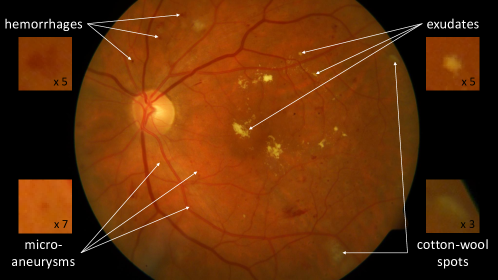

Retinal pathologies are responsible for millions of blindness cases worldwide. The leading causes of blindness are glaucoma (4.5 million cases), age-related macular degeneration (3.5 million cases) and diabetic retinopathy (2 million cases).111www.who.int/blindness/causes/priority Early diagnosis is the key to slowing down the progression of these diseases and therefore preventing the occurrence of blindness. In the case of diabetic retinopathy (DR) screening, diabetic patients have their retinas examined regularly: a trained reader searches for the early signs of the pathology in fundus photographs (see Fig. 1) and decides whether the patient should be referred to an ophthalmologist for treatment. In order to reduce the workload of human interpretation, and therefore streamline retinal pathology screening, various image analysis algorithms have been developed over the last few decades. The first solutions were trained to detect lesions (at the pixel level) using manual segmentations (at the pixel level) for supervision (Winder et al., 2009; Abràmoff et al., 2010): this is what we call computer-aided detection (CADe) algorithms. Based on the detected lesions, other algorithms were trained to detect pathologies (at the image level) (Abràmoff et al., 2010): this is what we call computer-aided diagnosis (CADx) algorithms. In recent years, new algorithms were designed to detect pathologies directly, using diagnoses (at the image level) only for supervision: these algorithms are based on multiple-instance learning (Quellec et al., 2017; Manivannan et al., 2017) or deep learning (LeCun et al., 2015). Because manual segmentations are not needed, such algorithms can be trained with much larger datasets, such as anonymized archives of examination records. The next challenge is to detect lesions using diagnoses only for supervision. Besides access to large training datasets, such an approach would allow discovery of new biomarkers in images, since algorithms are not limited by the subjectivity of manual segmentations. A few multiple-instance learning algorithms, supervised at the image level, can already detect lesions (Melendez et al., 2015; Quellec et al., 2016b). However, to our knowledge, no deep learning algorithm was designed to solve this task. The primary objective of this study is to find a way to detect lesions, or other biomarkers of DR, using deep learning algorithms supervised at the image level. A secondary objective is to use these local detections to improve DR detection at the image level.

5.3.2 DiaretDB1 Dataset

The second dataset consists of 89 color fundus photographs collected at the Kuopio University Hospital, in Finland (Kauppi et al., 2007). Images were captured with the same fundus camera, a ZEISS FF450plus digital camera with a 50 degree field-of-view. Images all have a definition of 1500 x 1152 pixels. Independent markings were obtained for each image from four medical experts. The experts were asked to manually delineate the areas containing microaneurysms (or ‘small red dots’), hemorrhages, hard exudates and cotton wool spots (or ‘soft exudates’) and to report their confidence ( 50 , 50 , 100 ) for each segmented lesion. Based on these annotations, only five images in the dataset are considered normal: none of the experts suspect these images to contain any lesions.